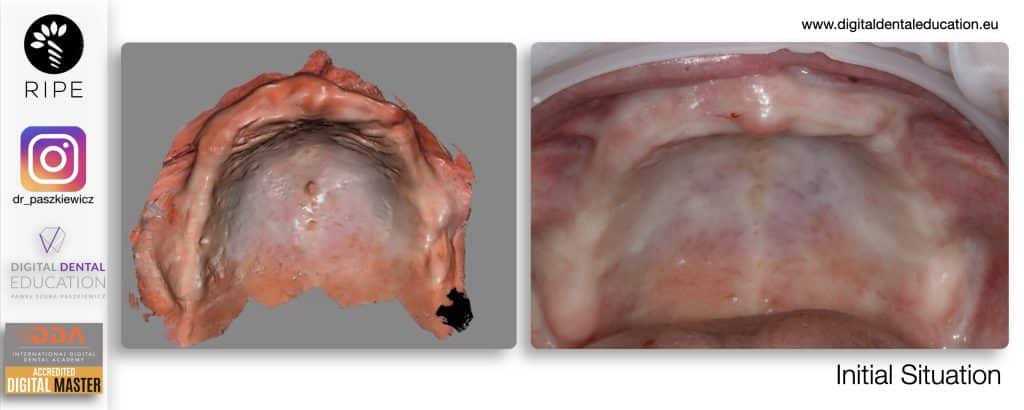

He has invented an AllonX non-impression protocol leading to final restorations post immediate implant full-arch loading, incorporated with desktop scanner (MEDIT) and ModJaw capturing of natural patient’s functional and mastication movements.